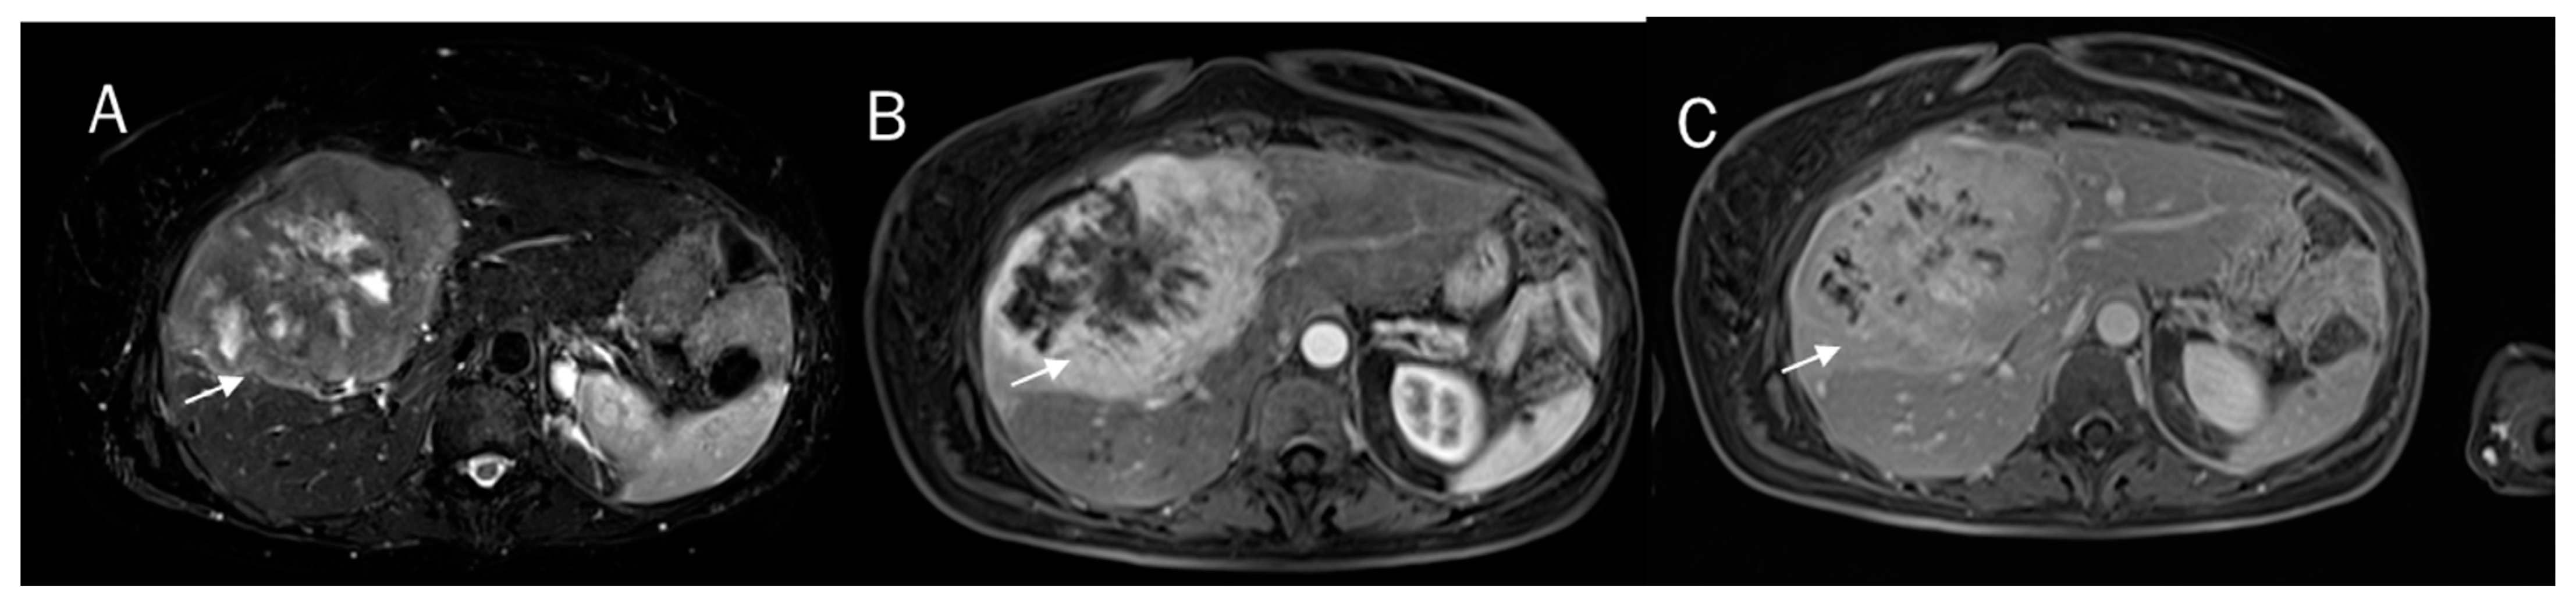

- Granata, V.; Fusco, R.; Venanzio Setola, S.; Sandomenico, F.; Luisa Barretta, M.; Belli, A.; Palaia, R.; Tatangelo, F.; Grassi, R.; Izzo, F.; et al. Major and ancillary features according to LI-RADS in the assessment of combined hepatocellular-cholangiocarcinoma. Radiol. Oncol. 2020, 54, 149–158. [Google Scholar] [CrossRef]